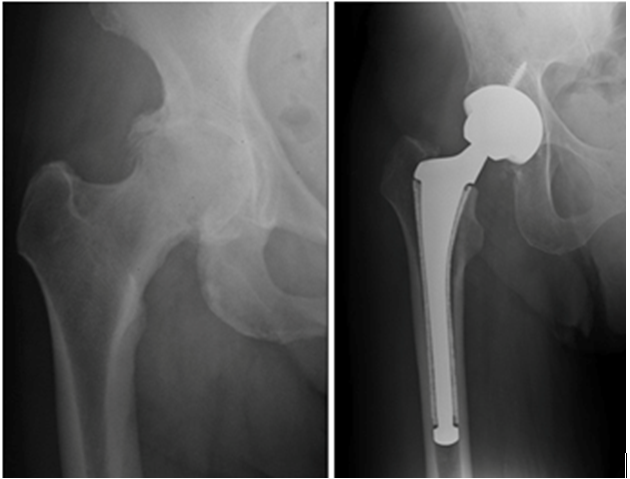

The company ORTHOPEDIC NIKIFOROV was founded in 1998 by the candidate of medical sciences. doctor of orthopedic-traumatologist of the highest category Nikiforov IA Owing to high professionalism and results of work, ORTONIC has gained well-deserved reputation and reputation among colleagues and population of Dnepropetrovsk region and CIS countries (Russia, Moldova, Armenia, etc.). The principle of the enterprise is NO IMPOSSIBLE, it is based on knowledge, experience and active implementation of modern technologies in orthopedics and traumatology. Conservative methods of treatment include individual selection of medicines, therapeutic blockades, manual therapy, massage, physiotherapy (vibration table, magnetotherapy, bioptron, electromyostimulation, etc.), rehabilitation with the suggestion of the necessary concomitant devices and means for the fastest recovery (corsets, bandages, various joint fixators, crutches, walking sticks, etc.). Various minor invasive interventions (chymonucleolysis, vertebroplasty, kyphoplasty, percutaneous nucleoplasty using cold plasma) that are performed on an outpatient basis are successfully used to treat problems associated with spine pathology. The latest modern treatment methods introduced in our company are endoscopic operations using the TYSSES technique of Joimax (Germany) with intervertebral hernias, stenosis and other pathologies of the spine, which allow to avoid complications occurring during open operations and the accompanying general anesthesia. We have many years of successful experience in traditional and modern minimally invasive endoprosthetics of large and small joints, which remains the main direction of our activity. Our company is the exclusive representative of the German company IO International Orthopaedics Holding GmbH, which based on the already known prostheses, its ideas and technological capabilities, has developed and implemented a new concept in hip replacement - an artificial joint prosthesis (ICON). We assist interested colleagues in training the operative technique for installing an artificial joint prosthesis - ICON, both in the workplace and in Germany. For 20 years we have been successfully cooperating with Sanitatshaus Gerd Klinz ortho team, an enterprise that for 20 years has been one of the leading places in Germany for the production of functional prostheses of the upper and lower limbs, as well as cosmetic prostheses of limbs and other body parts (nose, ears, eyeballs, fingers). We have an atmosphere of friendliness and human participation. Politeness, benevolence, the desire to understand and help is the basis of our attitude towards patients. We are always glad to see you and will do our best to make you feel great! We are waiting for you at: Ukraine, Dnepr, Gagarin Ave., 13 (under reconstruction) on all questions to address: tel .: +38 (050) 488-88-92 E-mail: orthonik.ukr@gmail.com Germany, Spine Nano Klinik, Zeppelinstr. 21, Potsdam Tel. +4901801121919 E-mail: kmw.nikiforov@hotmail.de